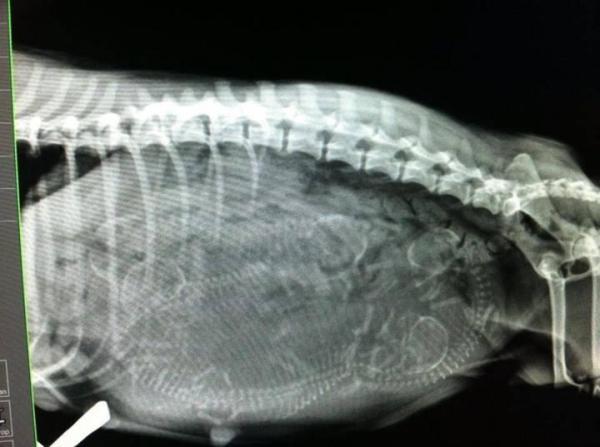

Dog panting after giving birth

After reviewing the different phases that make up a dog’s delivery process, it’s normal to understand why a dog may be panting after giving birth; exhaustion. This is especially common in dogs that breed more than 3 puppies. Incredible effort is needed by a bitch to expel her puppies, therefore, panting or a dog shaking after giving birth is often caused by this released energy. It is, however, incredibly important to check how many puppies have been born, making sure that your female dog has managed to expel all of them properly.

Eclampsia in dogs usually occurs 2-4 weeks after labor, so, if your bitch is panting a lot straight after giving birth, we can conclude that it is not milk fever. Remember that during canine pregnancy, it is possible that sometimes more puppies are birthed than what was originally expected. Therefore, if your dog is panting after giving birth, it may be because she is not done. If this situation lasts more than a few hours or your dog is struggling to expel the puppy, you should contact a veterinarian. It is crucial to monitor her closely during this time to ensure both her health and the puppies'.